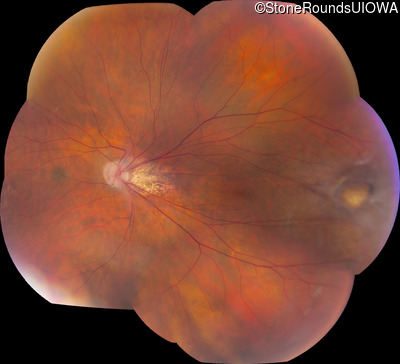

AD Familial Exudative Vitreoretinopathy (IIIE2b)

Age at visit: 32 years

This 32 year old woman has had subnormal acuity (right eye worse than left eye) since very early childhood.

AD Familial Exudative Vitreoretinopathy TSPAN12 Arg50Trp AG(G)>TG(G)   AD